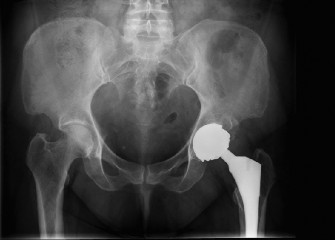

A 73-year-old man with a history of hypertension and hyperlipidemia presents to your office with right hip pa…

A 50-year-old female underwent metal-on-metal (MoM) total hip arthroplasty 1 year ago for osteoarthritis. Her…